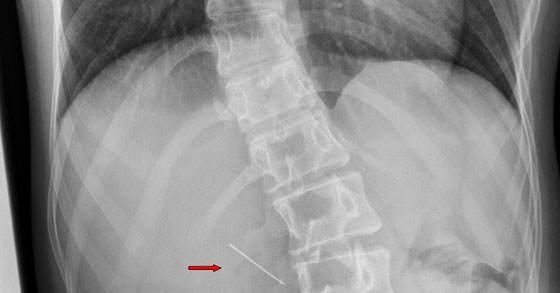

قام اخضائيو مركز شنايدر لطب الأطفال من مجموعة خدمات الصحة الشاملة كلاليت هذا الاسبوع باخراج ابرة من جدار معدة فتاة في الـ 17 من عمرها. الفتاة وصلت الى غرفة الطوارئ في مركز شنايدر بعد ان ابتلعت دبوس كانت تمسكه بين اسنانها في الوقت الذي كانت ترتب فيه الحجاب، عند تصوير البطن تبين وجود دبوس ذو راس دائرية في جدار معدة الفتاة. وجود الدبوس في المعدة من الممكن ان يؤدي الى نزيف، التهابات ومضاعفات اخرى.

تم نقل الفتاة بسرعة الى معهد امراض الجهاز الهضمي، التغذية وامراض الكبد في مركز شنايدر برئاسة البروفيسور رعنان شمير. بعملية المنظار التي اجريت للفتاة وهي في حالة تخدير كامل والتي قام بها الدكتور نوعم زبيط، طبيب في قسم امراض الجهاز الهضمي، مع الدكتور ايلي سمحا، طبيب مخدر ومدير وحدة الانعاش في مركز شنايدر وبمساعدة الممرضة حافا فليشهكر، تم العثور على الدبوس مغروزة عميقا في جدار المعدة، ممتصلة مع الإثنا عشر.

تم اخراج الدبوس بواسطة تطويق جدار المعدة واخراجها بدقة وحذر من خلال المريء في الحنجرة، حيث تم اخراج الدبوس بواسطة ملقط خاص. تم اخراج الفتاة من المستشفى بعد ان تحسنت حالتها بسرعه.